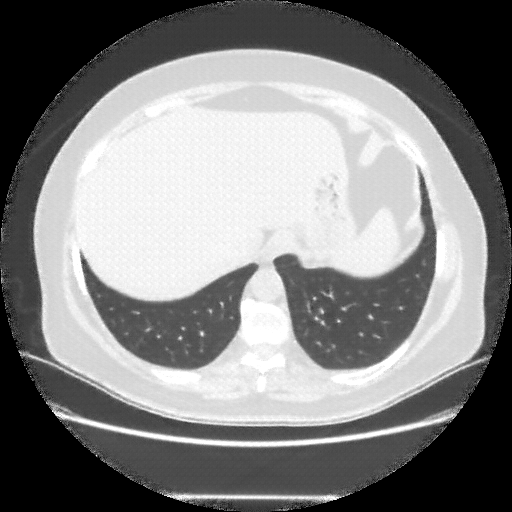

Targeted Slice 70 - Mediastinum Window Analysis (Generated vs Real Venous)

0.683

Mediastinum SSIM

32.8

Mediastinum RMSE

14.7

Mediastinum MAE

Average Mediastinum Window Metrics Across All Slices (25 slices) - Generated vs Real Venous

0.660

Mediastinum SSIM (Avg)

37.3

Mediastinum RMSE (Avg)

17.4

Mediastinum MAE (Avg)

Generated VENOUS CT scan (A→B translation)

Mediastinum window (WL 40, WW 400 β†’ Low βˆ’160, High +240)